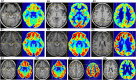

Purpose: There are few studies on the glucose metabolic characteristics of the extra-hypothalamic cortex in the hypothalamic hamartomas (HH). A comprehensive understanding of pathogenic progression of the disease is required from the perspective of cortical metabolism; therefore, we aimed to characterize metabolic characteristics of extra-hypothalamic in HH patients. Methods: We investigated the metabolic characteristics of 16 HH patients, all of whom underwent epilepsy evaluation at Xuan Wu Hospital between 2017 and 2019. The lateralization and cortical distribution pattern of hypometabolism was assessed and related to HH mass neuroanatomy on magnetic resonance imaging (MRI) as well as scalp-electroencephalogram (scalp-EEG) abnormalities. Furthermore, asymmetry measurements of region of interest (ROI) in the temporal cortex (hippocampal formation, amygdala, and lateral temporal neocortex) were quantitatively assessed based on the normalized average positron emission tomography (PET) voxel values. The surgery prognosis was assessed using the International League Against Epilepsy (ILAE) classification system. Results: The lateralization of hypometabolism in global visual ratings was consistent with the HH mass lateralization seen on MRI. Cortical hypometabolism showed three patterns depending whether the HH mass involved mammillary bodies, middle hypothalamus nucleus, or both. The three patterns were hypometabolism of the mesial temporal cortex with symptom of mesial temporal epilepsy (3/16, pattern I), lateral temporal, and extratemporal (frontal or parietal) cortex with symptom of neocortex temporal or frontal epilepsy (5/16, pattern II), and mesial and lateral temporal cortex and extratemporal (frontal or parietal) cortex with varied symptoms (8/16, pattern III), respectively. A significant difference in PET voxel values was found between bilateral hippocampal formation (P = 0.001) and lateral temporal neocortex in the third group (P = 0.005). We suggest that the hypometabolic characteristics of the extra-hypothalamic cortex in HH patients have three patterns. The final cortical hypometabolic pattern depends on the neuroanatomic location of the HH mass and was consistent with the main involved cortex of the interictal and ictal discharges. The third hypometabolic pattern with the most extensive cortical hypometabolism has a poorer prognosis.